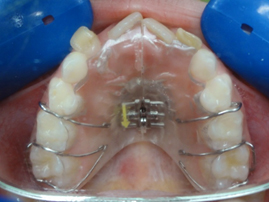

Plaque à verin vue de dessous

Elle est constituée d’une grande partie en résine qui a la forme du palais, d’un vérin au milieu, et de crochets qui permettent le maintien de l’appareil. L’activation du vérin permet d’élargir la mâchoire.